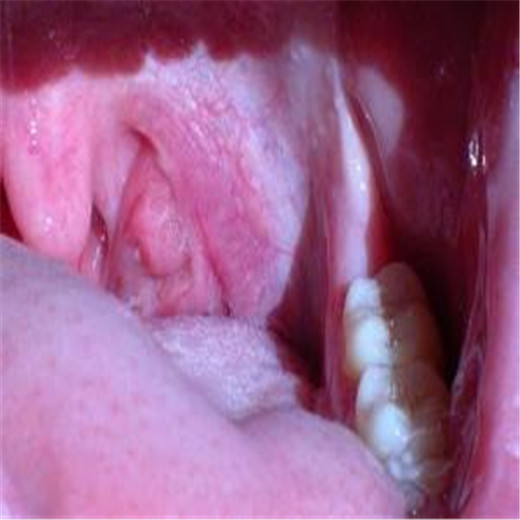

扁桃體炎圖片

扁桃體腫大